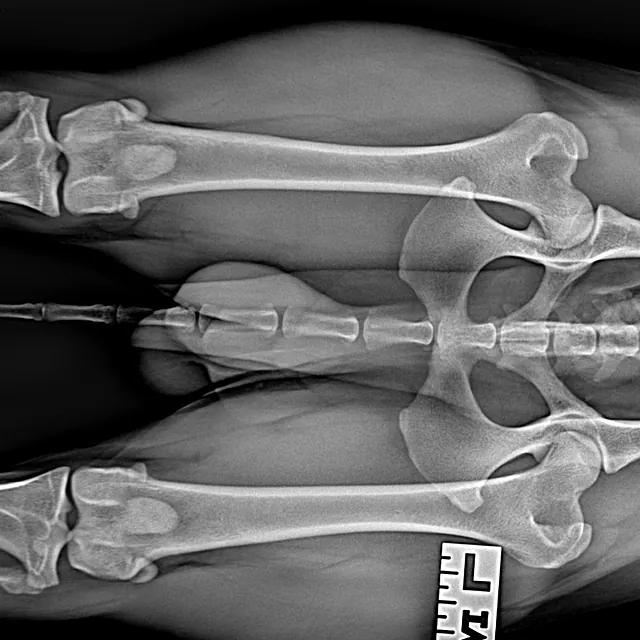

Hieronder foto's van Guus genomen met onze nieuwe DRgem rontgen. Beoordeeld met de hoogste score door de Raad van Beheer op Kynologisch gebied

Heupdysplasie onderzoek

Heupdysplasie is een ontwikkelingsstoornis van de heupgewrichten, deze aandoening kan erfelijk zijn, maar omgevingsfactoren spelen soms ook een rol. Een hond hoeft geen last te hebben van HD, dus aan de buitenkant kunt u niet zien of een hond HD heeft. Als uw hond goed kan lopen, wil dit niet zeggen dat er geen HD speelt. Om dit met zekerheid te kunnen beoordelen zijn röntgenfoto’s van de heupen nodig.

Meestal passen wij een sedatie toe bij het maken van de officiële HD-foto’s. Dit is nodig om een kwalitatief goede foto te maken, welke aan de hoge eisen van de beoordelingscommissie moet voldoen. Uw hond moet op zijn of haar rug liggen, waarbij het bekken en de achterpoten symmetrisch worden gestrekt en de knieschijven moeten op juiste manier worden ingedraaid.